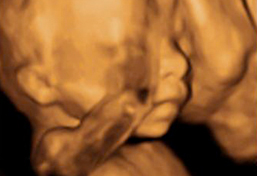

Para muchas personas, una ecografía es simplemente un momento técnico de control del embarazo. Pero en algunos casos la imagen revela algo inesperado —una forma que parece una mano apoyando al bebé— y se interpreta como “la mano de Dios”. Este fenómeno, aunque puede tener explicaciones médicas (ángulo, sombra, volumen de líquido), adquiere un valor simbólico muy potente: protección, presencia divina, cuidado y consuelo. En este artículo exploramos el significado de esta imagen, qué podría transmitir a nivel emocional y espiritual, y cómo responder ante ella.

- Una ecografía es una imagen médica que representa tejidos, líquido amniótico, posiciones del feto. A veces, las “formas” que parecen manos, rostros o figuras divinas son resultado de ángulos, sombras, volumen del líquido.

- Que la imagen se interprete como “la mano de Dios” depende de la fe, la cultura, la historia personal de quienes la reciben. Para unos será un milagro; para otros, una curiosidad visual.

Ver la “mano de Dios” en una ecografía no es solo ver una forma: es percibir un símbolo que puede transformar tu experiencia de embarazo, tu relación con el bebé, tu sentido de protección y tu esperanza en el mañana. Aunque la interpretación dependa de tu mirada, el valor que le otorgues puede acompañar todos los días del embarazo y más allá.